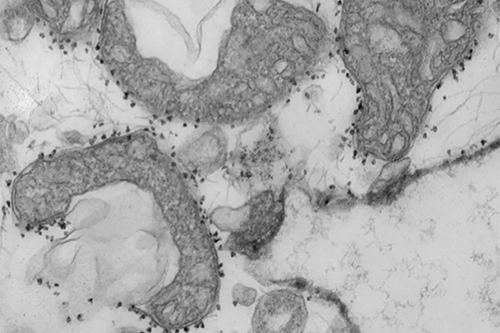

ÏßÁ£ÌåDNAˮƽÊÇ×éÖ¯ËðÉ˵ÄÁ¿¶È¡£¡£¡£¡£¡£Í¼Îª´ÓÈË·ÎÊͷŵÄÊÜËðÏßÁ£Ì壨Éî»ÒÉ«ÇøÓò£©¡£¡£¡£¡£¡£ÏßÁ£ÌåÖÜΧµÄСºÚµãÊÇ´ÅÐÔÖé×Ó£¬£¬£¬£¬£¬£¬ÉÏÃæ´øÓп¹Ì壬£¬£¬£¬£¬£¬ÕâЩ¿¹ÌåÓÃÓÚ¸ôÀëºÍÑо¿ÒÑ´ÓÃÖÁôµÄ×éÖ¯ÖÐÊͷųöÀ´µÄ²»¿µ½¡µÄÏßÁ£Ìå¡£¡£¡£¡£¡£

£¨Í¼Æ¬ÈªÔ´£ºWandy Beatty£©